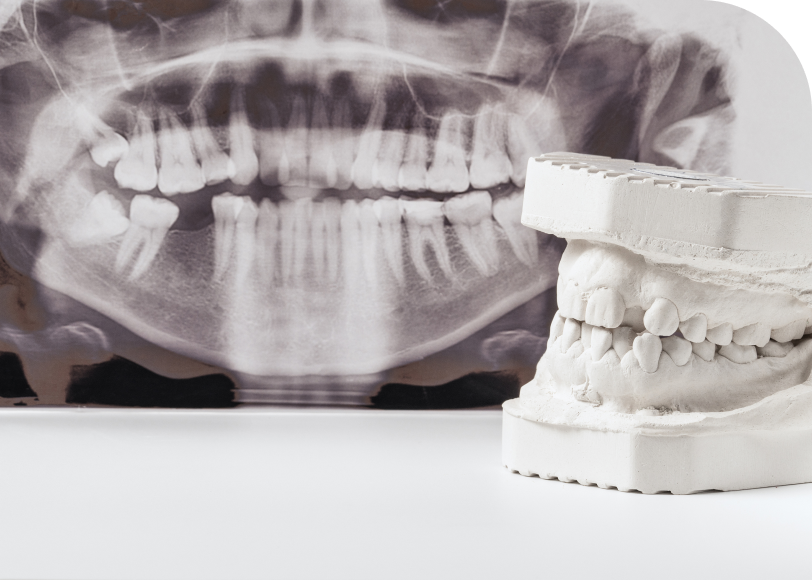

Le dentiste commence par un examen clinique. Ensuite, il prescrit une radio panoramique, parfois un scanner 3D. Ces images permettent de visualiser l’os, la gencive et l’espace disponible.

Lorsque l’os paraît insuffisant, le praticien peut proposer une greffe. Dans ce cas, une période de consolidation est nécessaire avant la pose.